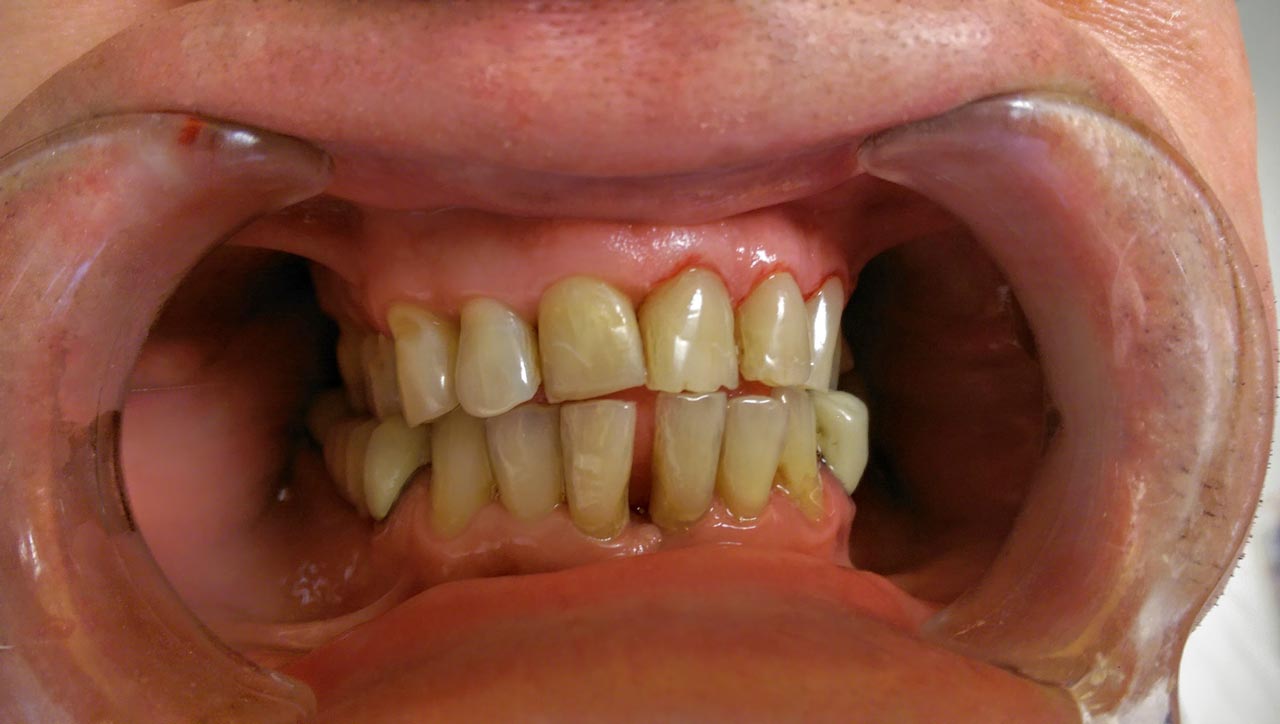

Elhanyagolt fogsor cseréje 2 nap alatt

2 nap alatt varázsoltuk ezt a szép esztétikus alsó, felső körhídat implantátumokkal megtámasztva a korábban elhanyagolt szájba. Az 1. nap 26 fogat távolítottunk el, mert annyira rossz állapotban voltak, és rögtön azonnal terhelhető IHDE svájci implantátumokat raktunk be, fentre 8, lentre 6 darabot. A sebeket összevarrtuk és intraorális szkennerrel digitális lenyomatot vettünk. 2 nap múlva pedig beragasztottuk a kész PMMA műanyag körhidakat. Dr. Kelemen Péter és a Symbion Fogtechnika munkája.